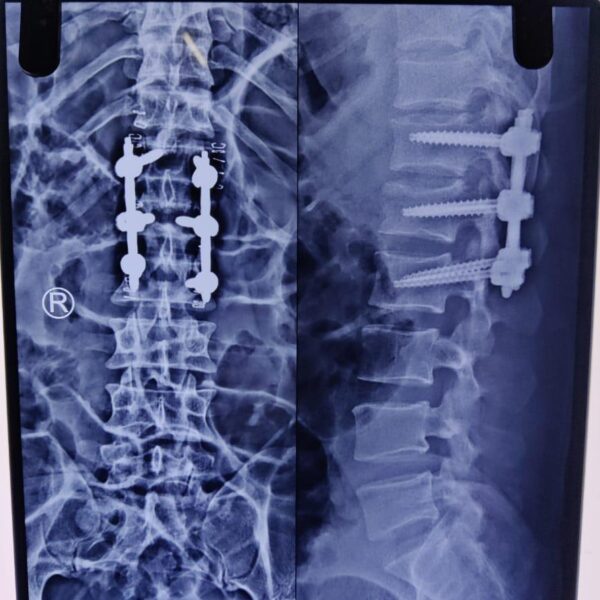

Moments That Mark Meaningful Recovery

Witness real patient transformations at The Ortho Clinic through images that reflect successful treatments and restored mobility.